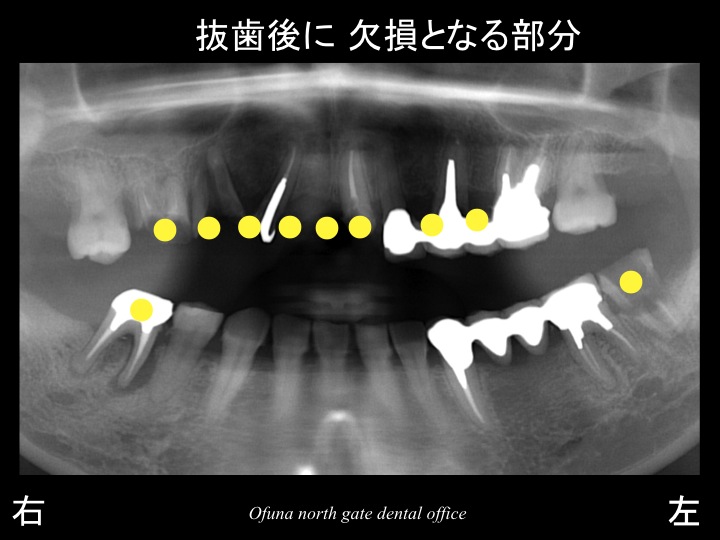

結論として、以下の×印の

虫歯が深かったり、歯根破折 している歯は 抜歯と診断されました。

抜歯後に歯がなくなる部位は、

上顎で8歯分、

下顎で3歯分(下顎右側の一番奥は始めから欠損しています)です。

大変な数の 歯がなくなることになります。

黄色丸の歯を土台として、固定式の仮歯を作製するのです。